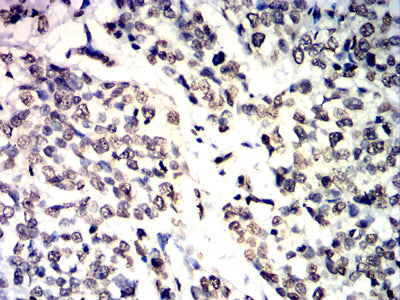

- Immunohistochemical analysis of paraffin-embedded human bladder cancer tissues using IL1B mouse mAb with DAB staining.

- Immunohistochemical analysis of paraffin-embedded human liver cancer tissues using IL1B mouse mAb with DAB staining.